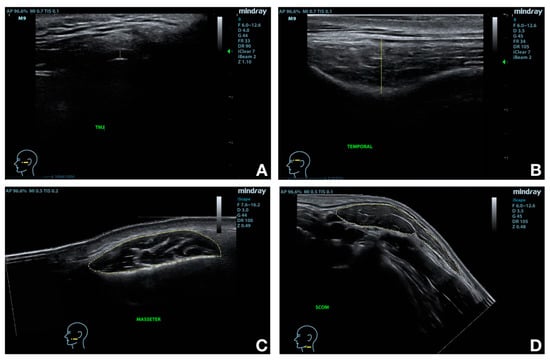

| Anatomical Structure | Outcome | Measurement Site/Procedure |

|---|---|---|

| Temporomandibular joint disc | Thickness | At the point between the glenoid fossa of the temporal bone and the mandibular condyle cortical surface, anteriorly to the tragus cartilage. Measured as the distance between the opposing surfaces of the disc. |

| Temporal muscle | Thickness | At the level of the temporal fossa, one centimeter laterally, and one above the lateral edge of the eye [9]. Measured as the distance between the opposing borders of the muscle, along the transverse axis of the muscle. |

| Masseter muscle | Thickness | At the proximal third of the distance between the ear cartilage and mandible angle, just below the inferior connection of ear to face [22]. Measured as the distance between the superficial and the deep border of the muscle. |

| Width | By a panoramic view function, moving the probe posteriorly-to-anteriorly following the curvature of the muscle and creating an image with an angle lower than 20°. Measured as the distance between the opposing extremities of the muscle along the transverse axis of the muscle. | |

| CSA | At the proximal third of the distance between the ear cartilage and mandible angle, just below the inferior connection of ear to face [22]. Evaluated by drawing the outline of the muscle on the image. | |

| Sternocleidomastoid muscle | Thickness | Before the carotid artery bifurcation [23]. |

| Width | By a panoramic view function, moving the probe anteriorly-to-posteriorly following the surface of the muscle and creating an image with an angle lower than 25°. | |

| CSA | Before the carotid artery bifurcation [23]. Evaluated by drawing the outline of the muscle on the image. |